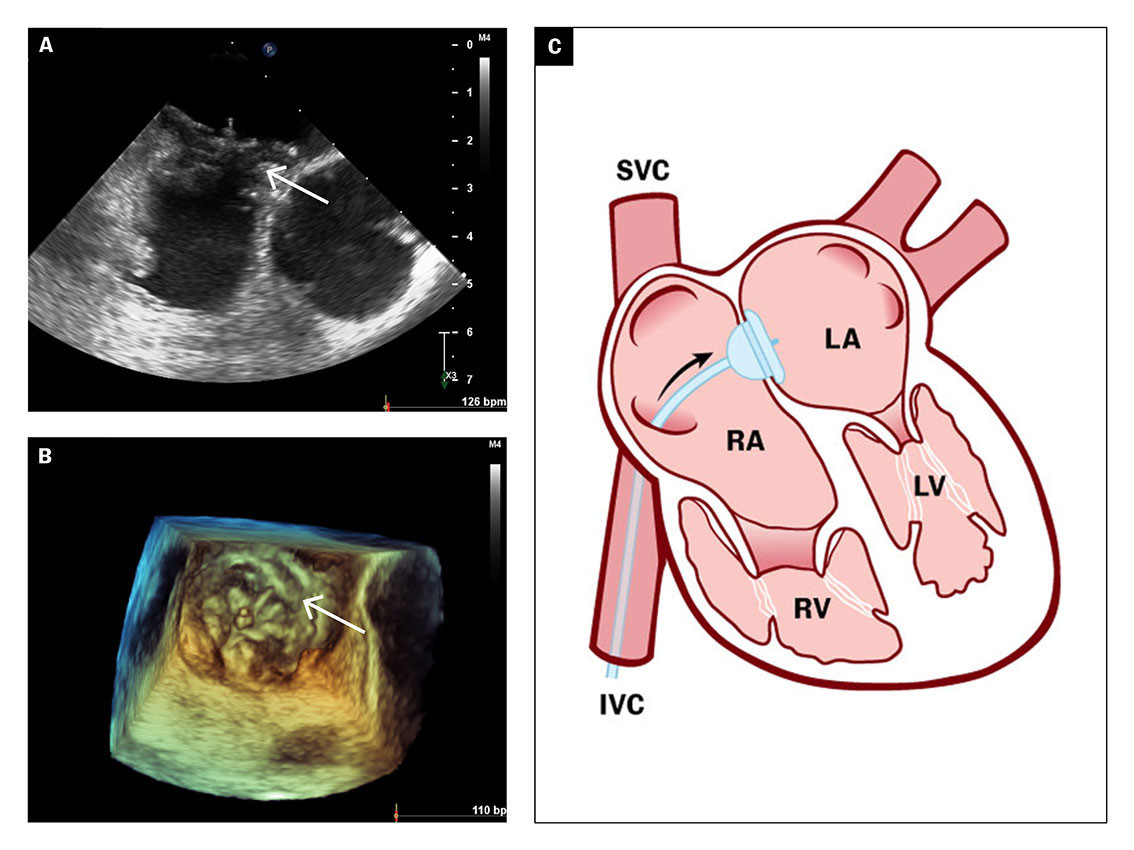

The transoesophageal echocardiogram showed patent foramen ovale with a tunnel length of 10 mm and an opening of 5 mm (Figure 3a), and a hypermobile atrial septum. Spontaneous right-to-left shunt of arterial emboli was observed using colour Doppler (Figure 3b).

The transoesophageal echocardiogram findings supported the suspicion of paradoxical embolisation with right-to-left shunt of atrial thrombus. Patent foramen ovale is usually verified by peripherally injected agitated saline and the Valsalva manoeuvre. Increased venous return to the right atrium would then cause a temporary increase in atrial pressure, which can lead to right-to-left atrial passage of microbubbles (Figure 3c).

Due to a clear spontaneous right-to-left shunt, no bubble test was performed on this patient. She was assessed for percutaneous catheter-based closure of the patent foramen ovale to reduce the risk of future arterial embolisation. As part of the investigation, an ultrasound of the deep veins was also performed. This revealed bilateral thrombi in the leg veins which were described as mobile and with a chronic appearance. A brain MRI and fundoscopic examination did not reveal evidence of recent cerebral or retinal embolic infarction.

After an eight-day hospital stay, the patient was discharged with anticoagulant therapy in the form of peroral apixaban tablets and referred for elective catheter-based closure of the patent foramen ovale. Balloon measurement of the patent foramen ovale revealed a short tunnel with a diameter of 15 mm, which was closed percutaneously with a 30 mm GORE Septal Occluder (Figures 4a–b), a self-expanding implant made of nitinol and GORE-TEX, with two surfaces that enable closure of the atrial septum on both sides (Figure 4c).